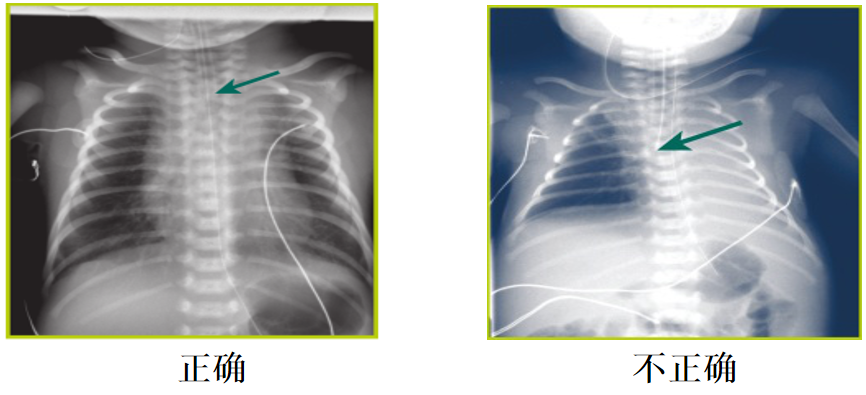

•X线胸片确认导管管端显示在:

锁骨或稍下水平

第二胸椎水平

喉镜镜片怎么选【新生儿复苏概论】中国新生儿窒息复苏项目标准(2020版)第五期:气管插管和喉罩气道_https://www.jmylbn.com_新闻资讯_第16张